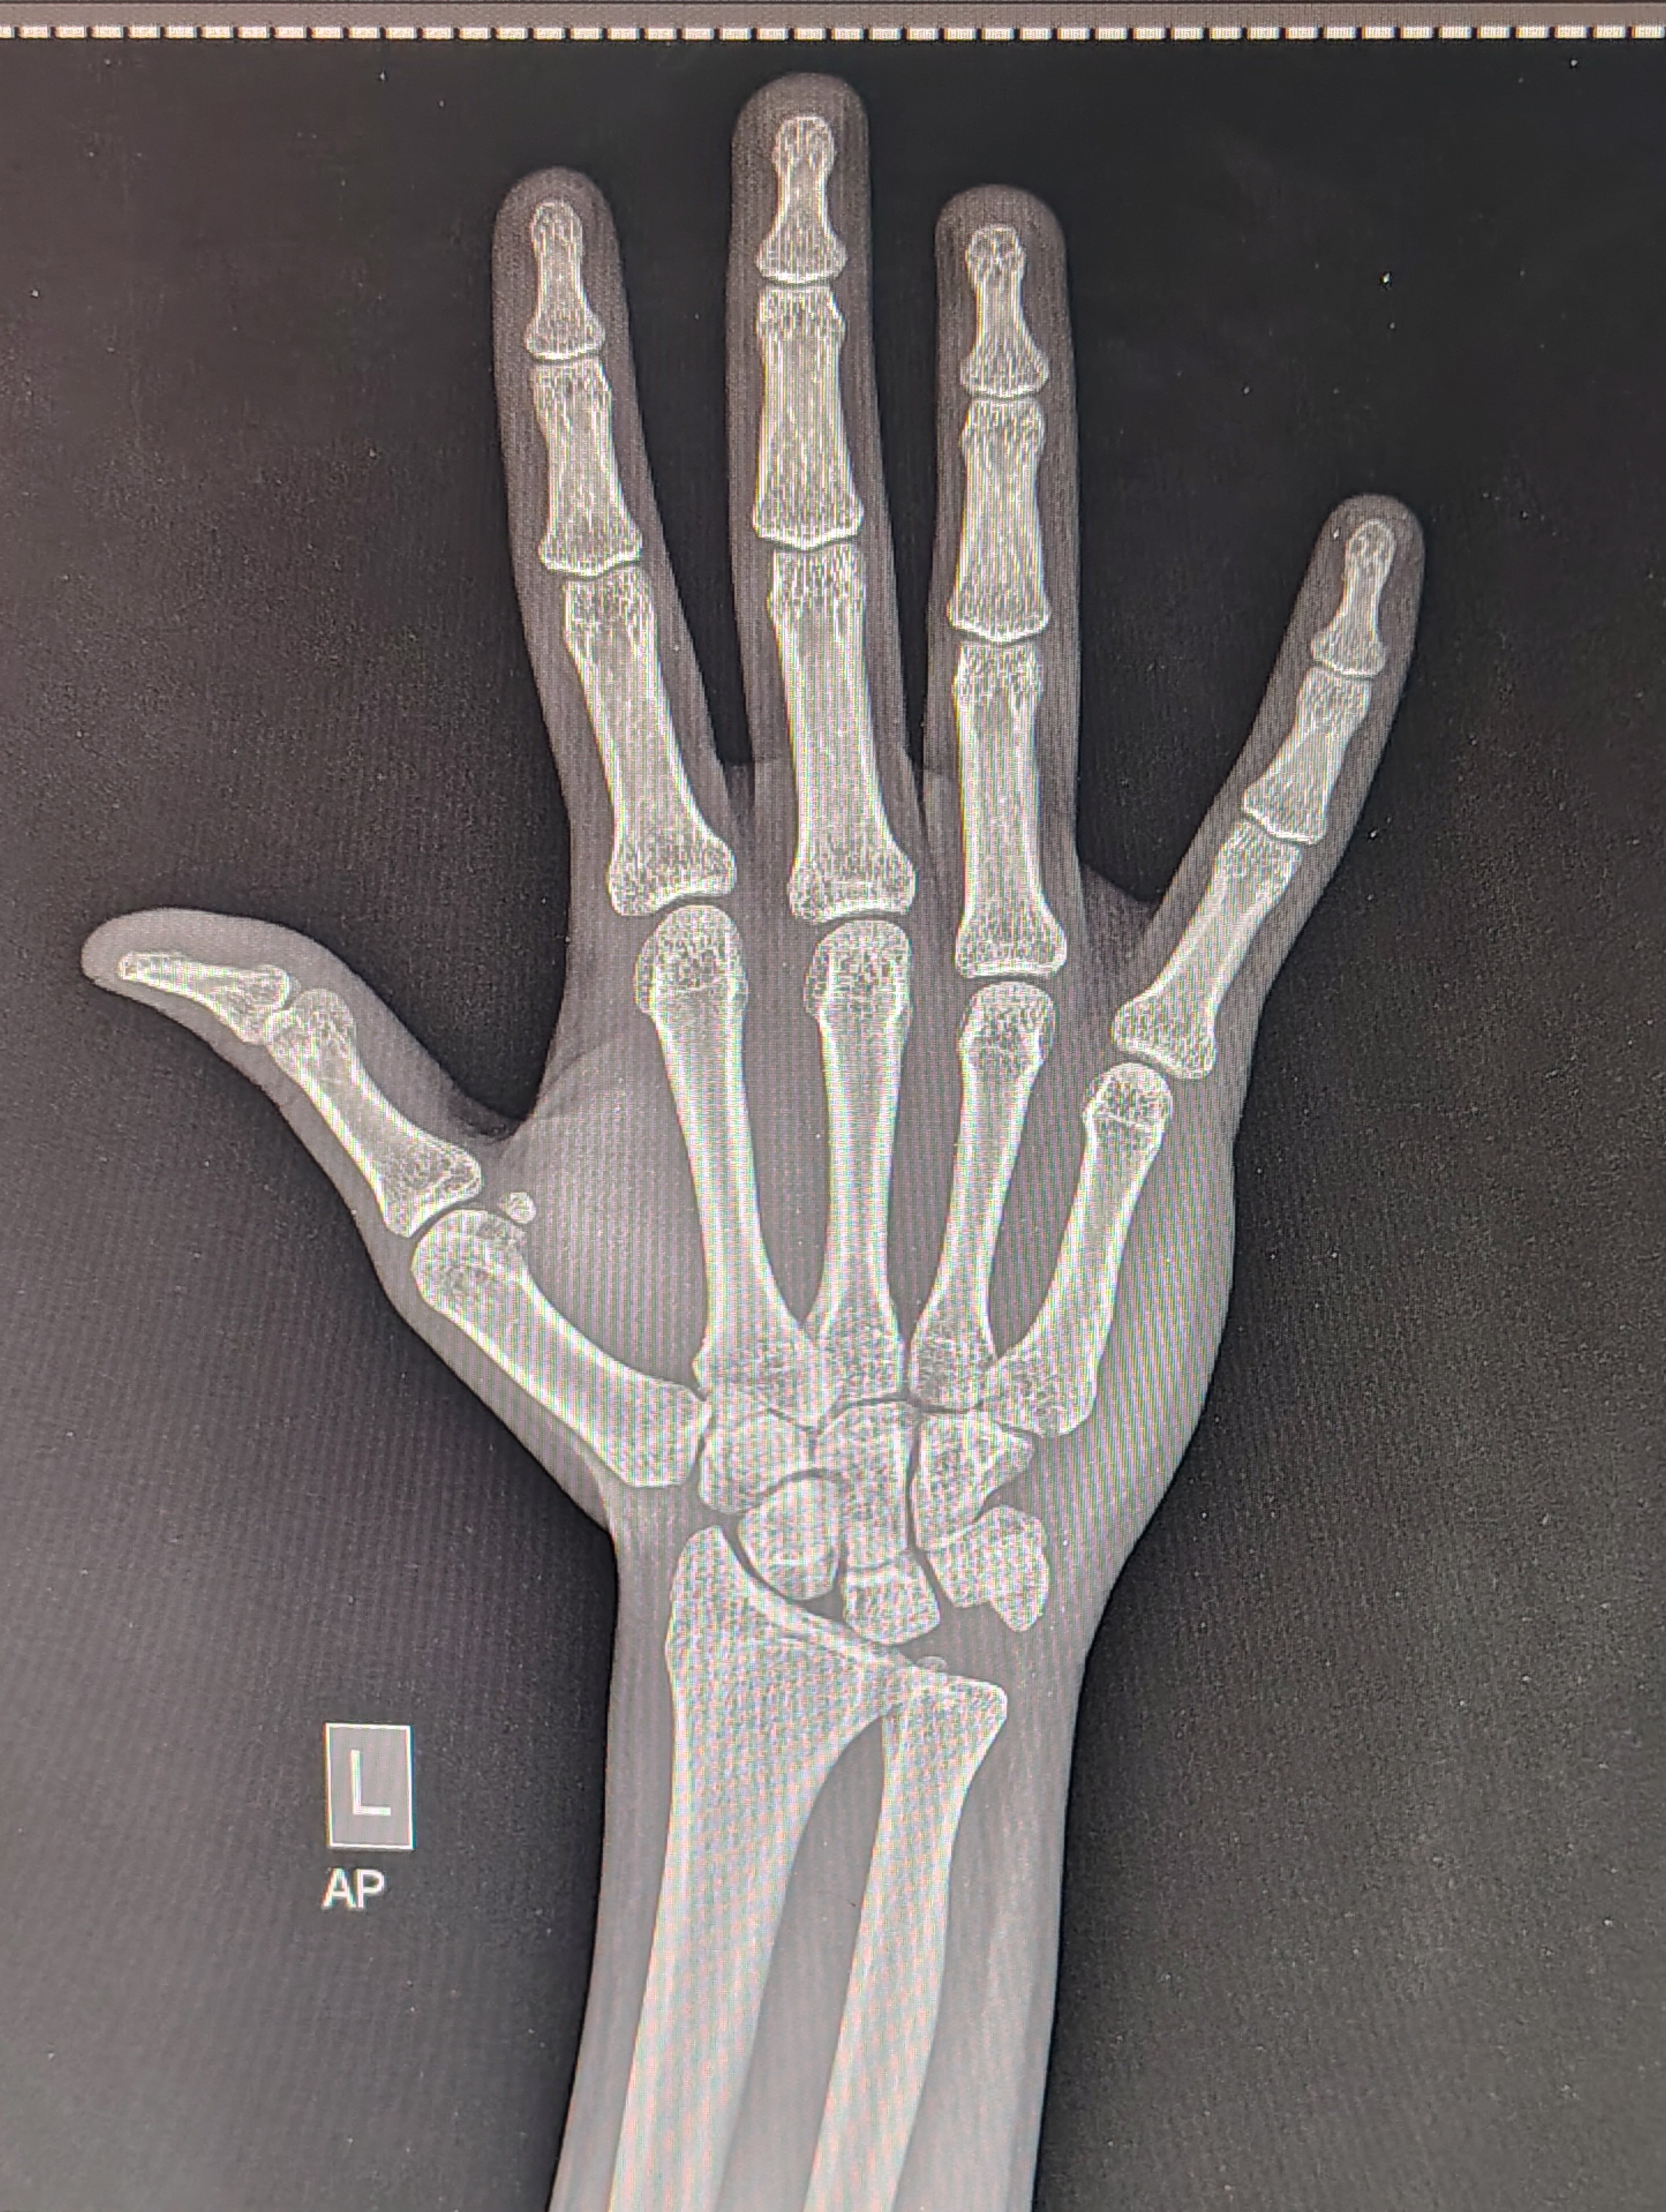

1000152629

look im not a dumbass I can see there are basically no growth plates left here ( just turned 18) but I just want to know if there's slightly any chance of growth for me and how my bones are looking cause my family has a history of bone fractures, calcium deficiency etc.

Your plates are fused, its not "basically" no open growth plates it's literally fully ossified

You're not growing anymore

What about my bone density

can't tell you with this xray, go get a DEXA scan if you care about your bone density for whatever reason